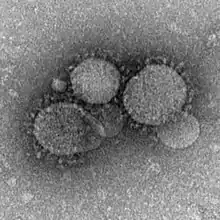

| MERS-CoV virions | |